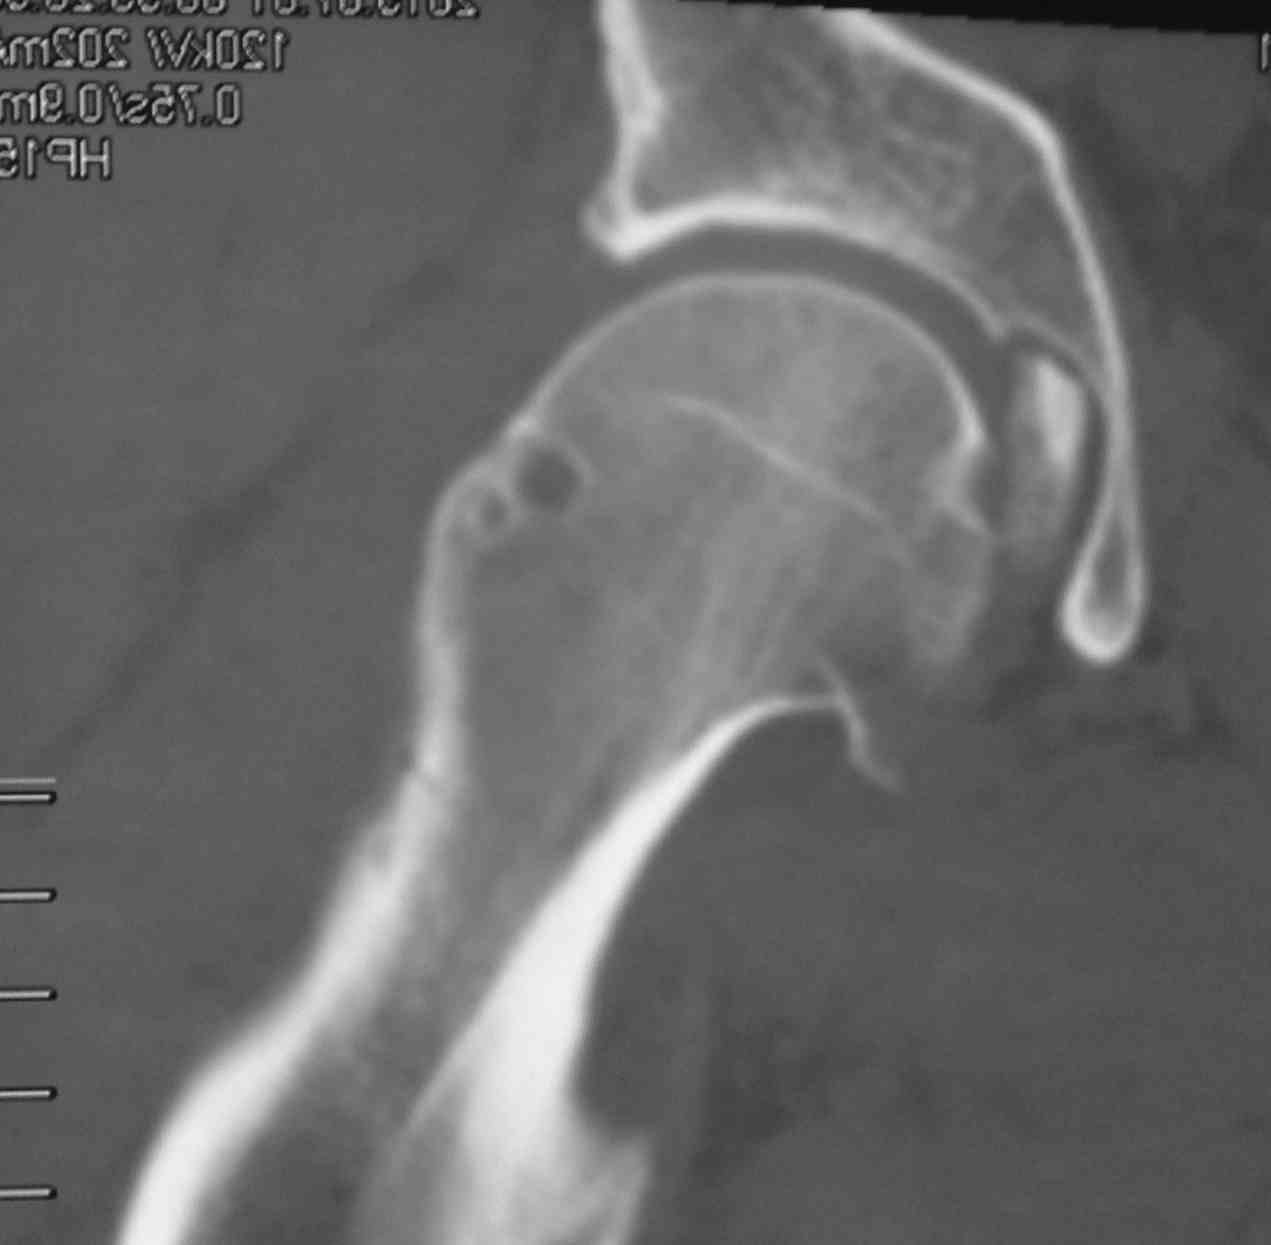

скан, который, на мой взгляд наиболее интересен

Серия КТ сканов в аппарате

Добрый день, коллеги! Повреждение вертлужной впадины вероятнее всего 62-А1.2 чистый переломовывих, оскольчатый перелом задней стенки, при этом внутрисуставной фрагмент, является частью артикулирующей поверхности ацетабулюм, а следовательно его необходимо извлечь и поместить на место, иначе мозаика может не собраться. Про FAI временно можно не вспоминать (не до него), поскольку наиболее тяжелое повреждение голени требует адекватного вмешательства.На представленных рентгенограммах таза после операции все отлично, полную картину даст КТ.

Голень-41-С3.1 - полный внутрисуставной и метафизарный оскольчатый перелом с доминантным повреждением наружного мыщелка, с импрессией центральной части плато. Первичная тактика полный респект по АО и ОТА. на фоне лигаметотаксиса выполнено КТ, которое четко детализирует повреждение и определяет дальнейшую тактику.

Основная проблема не бугристость, а внутрисуставное повреждение латерального мыщелка с импрессией центральной части. С большей вероятностью, есть паракапсуллярное продольное повреждение наружного мениска.